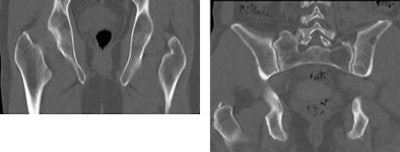

![]() |

| Thin-section whole-body MDCT in a low-dose 50 mAs protocol (41-year-old male, right) performed as well as a standard 100 mAs protocol (54-year-old male, left) for detecting osteolytic lesions. Mean image noise (24 HU) was higher for the low-dose images (12 HU), but image quality was rated excellent for both groups, and the radiation dose was far lower in the 50 mAs protocol. Images courtesy of Dr. Sonja Buhmann. |

The average cost of the CT exam (320 euros) fell between that of radiography (230 euros) and MRI (590 euros). While MRI is the gold standard, CT offers high-resolution imaging and display of the trabecular structure. The CT exam was also faster, and perhaps most important, CT picked up every lesion detected by MRI, Buhman said.

"All osteolytic lesions that were primarily detected on the gold-standard MRI were also detected using 50 mAs as well as 100 mAs CT," she said. Considering the accuracy and the low effective radiation dose, Buhman said, it may be advisable to choose low-dose CT in favor of radiography for initial skeletal assessment in patients with multiple myeloma. Even at 50 mAs, CT still provided good image quality.